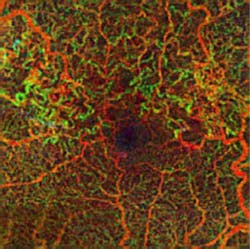

Zeiss Medical Technology (Dublin, CA) has received FDA clearance for its AngioPlex OCT angiography technology, which enables ophthalmologists to use optical coherence tomography (OCT) images to assess the blood vessels (vasculature) of the retina at a depth and clarity never available before. The technology delivers high-resolution, depth-resolved visualization of the separate layers of the retinal and choroidal vasculature without the need for an injected contrast dye, as is standard with fluorescein angiography (FA).

The information provided by these images is clinically impactful, because progression of retinal diseases is often accompanied by changes in the vasculature of the eye. In age-related macular degeneration (AMD), diabetic retinopathy, central retinal vein occlusion, and other vascular conditions, AngioPlex OCT angiography can complement traditional FA and become a safe and efficient part of routine eye care, potentially enabling earlier detection and management of micro-progressions.